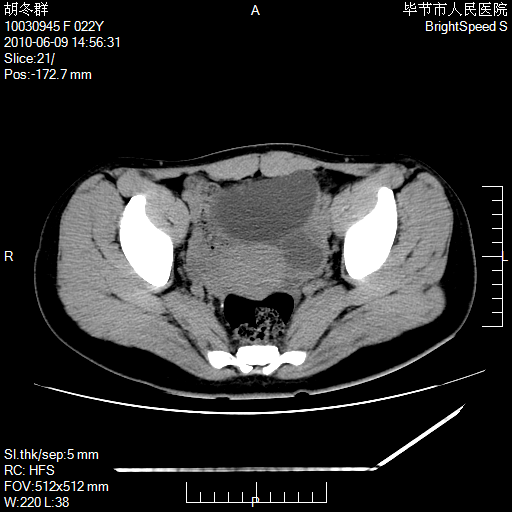

患者23岁,发现腹部包块3月。

盆腔内囊性占位;穿刺或者直接手术拿掉即可,不必紧张。

左侧卵巢囊腺瘤或囊腺癌

盆腔内囊性占位性病变;考虑左侧卵巢囊腺瘤。

有分隔、壁薄,支持考虑左侧卵巢囊腺瘤。

左侧卵巢浆液性囊腺瘤。

支持考虑左侧卵巢囊腺瘤;宫腔积液。